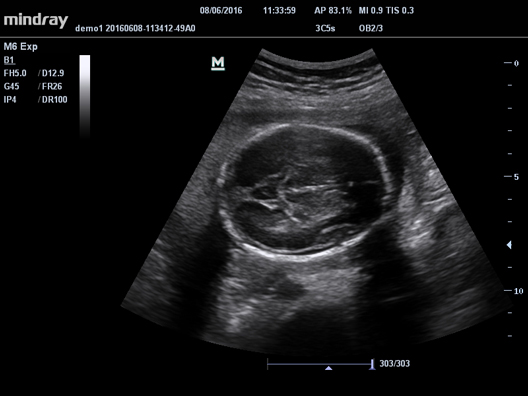

УЗ-сканер Mindray М6 exp представляет собой полнофункциональную портативную, размером с ноутбук, систему цветной допплерографии. Аппарат обеспечивает безупречную визуализацию в формате 2D. Оснащенная специализированными технологиями система М6 exp является оптимальным вариантом для применения.

Галерея изображений